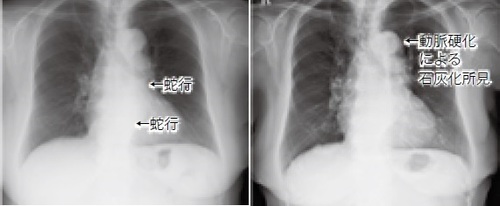

右:2003年3月(74歳)、左:2019年5月(90歳)

右:2009年3月(57歳)(大動脈弓部には石灰化がない)、左:2017年3月(65歳)(大動脈弓部に石灰化がある)。